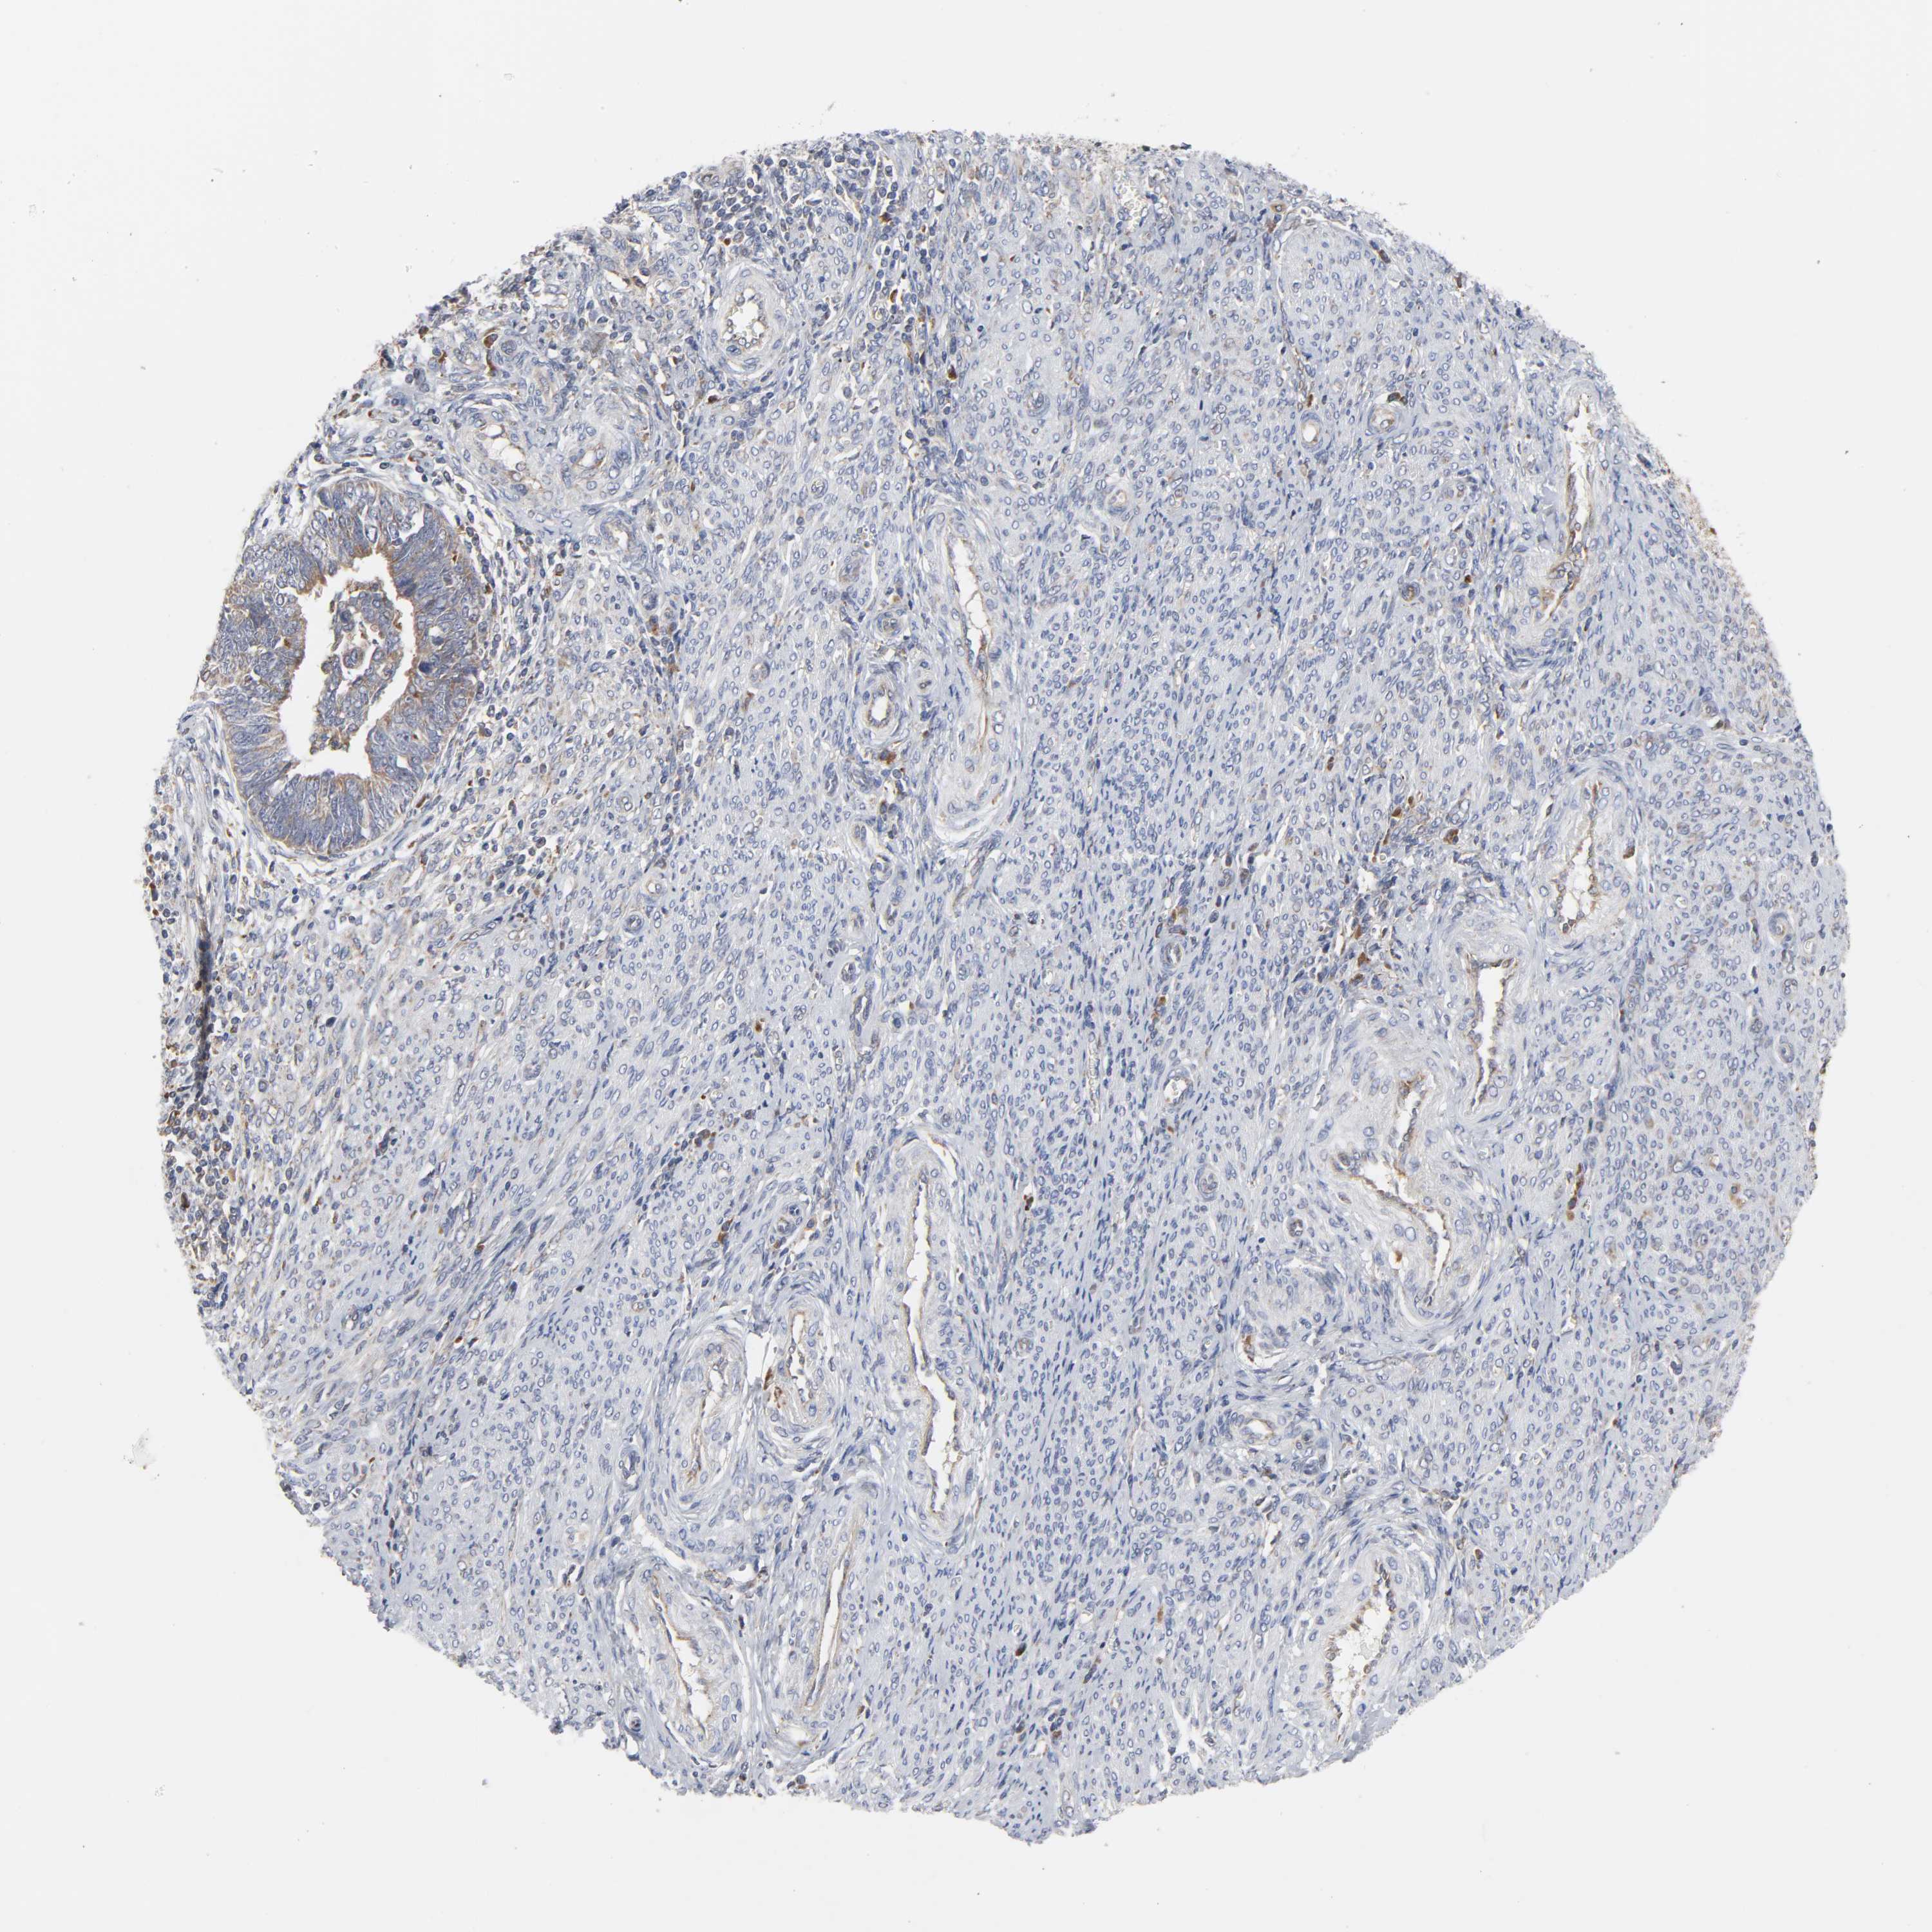

ENDOMETRIAL CANCER - Protein expressioni

A mouse-over function shows sample information and annotation data. Click on an image to view it in a full screen mode. Samples can be filtered based on level of antibody staining by selecting one or several of the following categories: high, medium, low and not detected. The assay and annotation is described here.

Note that samples used for immunohistochemistry by the Human Protein Atlas do not correspond to samples in the TCGA dataset.

Antibody stainingi

Antibody staining in the annotated cell types in the current human tissue is reported as not detected, low, medium, or high, based on conventional immunohistochemistry profiling in selected tissues. This score is based on the combination of the staining intensity and fraction of stained cells.

Each image is clickable and will lead to virtual microscopy that enables deeper exploration of all samples and also displays staining intensity scores, fraction scores and subcellular localization as well as patient and tissue information for each sample.

Antibody HPA027878

Antibody CAB004206

Staining

High

Medium

Low

Not detected

Intensity

Strong

Moderate

Weak

Negative

Quantity

>75%

75%-25%

<25%

None

Location

Nuclear

Cytoplasmic/membranous

Cytoplasmic/membranous,nuclear

Adenocarcinoma, NOS

Adenocarcinoma, metastatic, NOS

Neoplasm, malignant, NOS